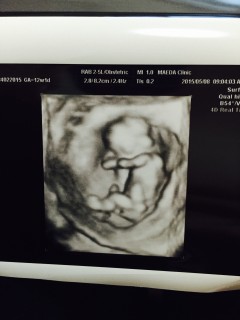

始めての4D~(^_^)こんなに綺麗に映るのは珍しいみたい!この形で丁度お腹の中にいるらしくてパパと感動した!可愛すぎるよ!!つわりもあとちょっとだしママ頑張るっ(^o^)